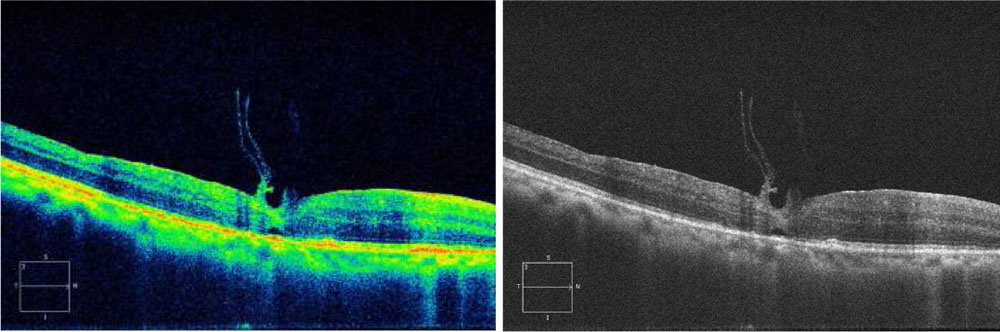

5. FP448 : Macular Plug: analysis of SDOCT Changes Leading on to Hole Closure.